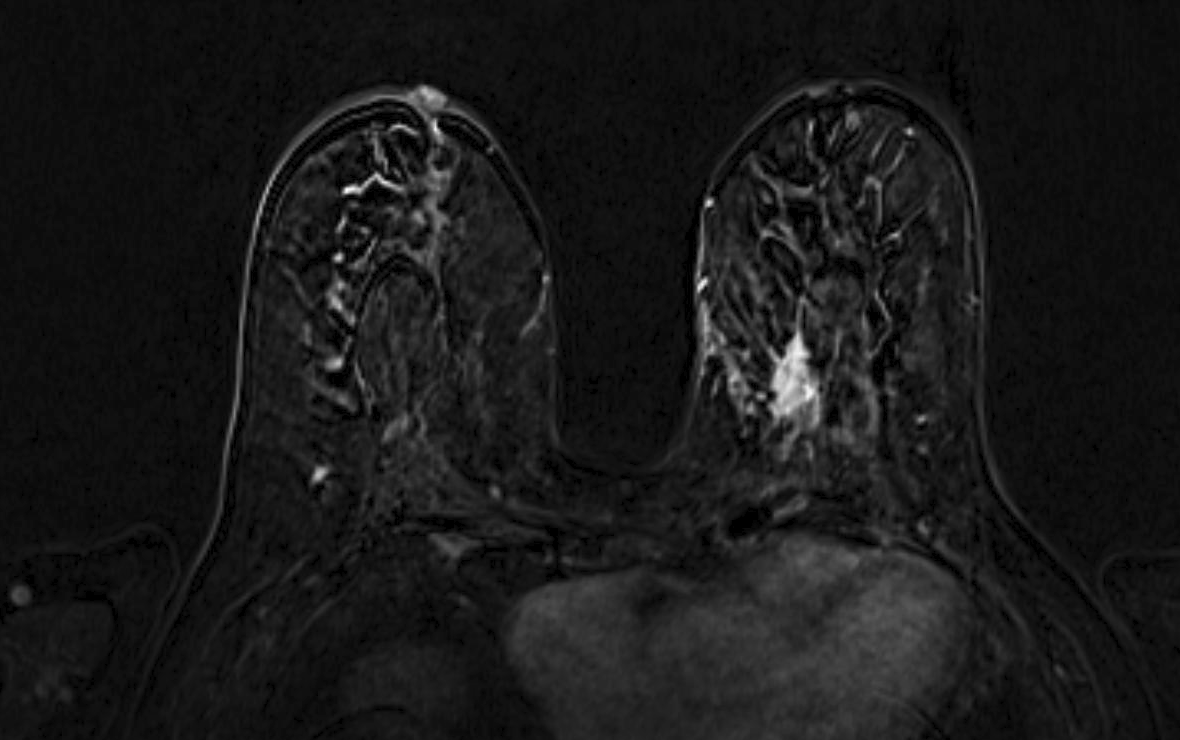

Magnetic resonance imaging (MRI) has been used as an adjunctive screening tool, mainly for women who may be at increased risk for the development of breast cancer. Example images of MRI are shown in fig. 5 with T1 contrast enhancement. MRI for screening has not been very popular in women with average risk due to concerns about the low specificity leading to additional biopsies, time and cost of technology [26]. Breast MRI sensitivity values reported in high risk screening studies range from 93% to 99%. Despite its high sensitivity, breast MRI has been reported to have variable specificity, ranging from 50% to 85% [27]. These number of sensitivity and specificity depends on the type of tumor, size of tumor, age of patient, and where it is localised.